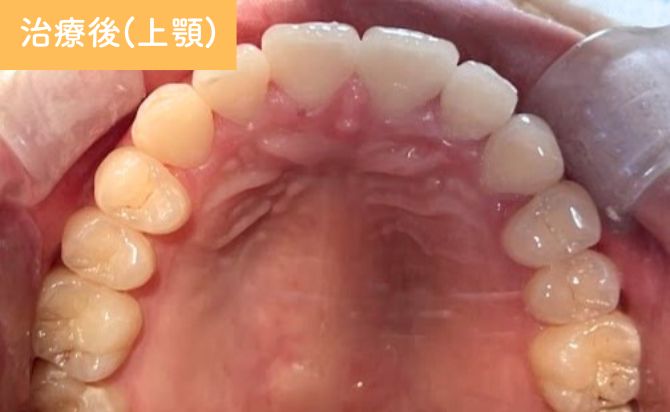

歯並びの変化(上)

治療終了時には、上顎前歯の前突が改善し、

唇元の突出感が軽減したことで横顔のバランスも向上しました。

歯列全体のアーチも整い、前歯の噛み合わせが適切な位置に改善。見た目だけでなく、機能的にも安定した咬合が得られています。